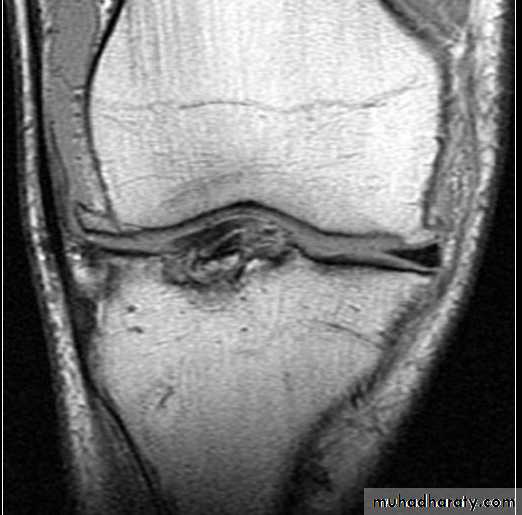

MRI

Pathology

Medial meniscus is less mobile more liable for injuryMost of the meniscus is avascular : tear not capable of healing except the lateral third

Meniscal tear mechanical irritation synovitis & later O.A.

Axial loading + flexion + rotationTypes of meniscal tear

Vertical longitudinalBucket – handle

TransverseOblique

Horizontal cleavage : degenerativeC / F